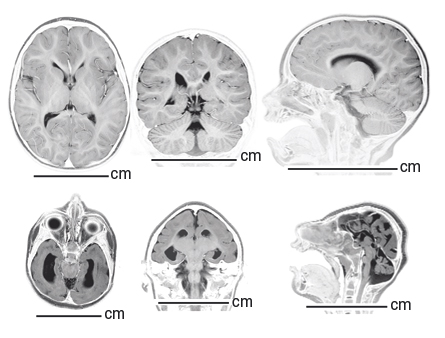

SMALL BRAIN Mutations in the NDE1 gene prevent cells from dividing normally, which may cause a severe reduction in brain size (lower row), shown here in MRI scans. Courtesy of Yale University School of Medicine

CTYPE html PUBLIC “-//W3C//DTD HTML 4.0 Transitional//EN” “http://www.w3.org/TR/REC-html40/loose.dtd”> Small brain mutation Mutations in a single gene are the cause of a rare genetic disorder that leaves children with a brain one-tenth the normal size, two international teams of researchers report April 28 in the American Journal of Human Genetics . To identify the mutations, researchers analyzed DNA from Turkish, Pakistani and Saudi Arabian families with children who had extremely underdeveloped brains. Affected children had mutations in a gene called NDE1 , both groups found. Cells without a working copy of the gene don’t correctly divide to form new cells, a defect that probably prevents the brain from growing normally in early development. Further studies of the gene might reveal clues to how humans evolved large brains, the researchers speculate. — Laura Sanders   Calcium linked to heart risks Researchers in Switzerland have correlated excess levels of calcium in the blood with a large and diverse set of risk factors for heart disease in a cross-section of 4,200 adults 35 to 75 years old. The strongest and most novel associations pointed to signs of oxidative stress. These markers included elevations in uric acid (responsible for gout), homocysteine (a marker of meat consumption) and the liver enzyme GGT. There’s no evidence that calcium consumption is itself a problem, the authors note in the April 21 PLoS One . Risks may trace instead, they say, to the body’s inappropriate management of the substance. — Janet Raloff   MS linchpin found in mouse tests A previously unknown kind of immune cell makes a protein that may be a pivotal player in multiple sclerosis, two studies in an upcoming issue of Nature Immunology show. The protein is an inflammation-causing immune agent called GM-CSF. In mice prone to MS-like disease, animals lacking the protein didn’t get sick, a Swiss team reports. Likewise, mice with a version of MS were cured of it when the GM-CSF protein was neutralized. A U.S. team also arrives at GM-CSF as a culprit in the disease and delineates how other immune cells and proteins appear to be involved in steps leading to MS, which is marked by an immune assault on protective sheaths that insulate nerves. —Nathan Seppa   HIV may increase heart failure risk People infected with HIV, the AIDS virus, may be more prone to developing heart failure, scientists report in the April 25 Archives of Internal Medicine . A study of more than 8,000 veterans who were monitored for a median of 7.3 years revealed 286 incidents of heart failure. The rate of heart failure incidents was 81 percent higher among HIV-positive participants. The U.S. team of researchers accounted for differences in age, race and ethnicity among the vets when conducting the analysis. Higher viral loads meant higher heart-failure risk, the scientists noted. — Nathan Seppa